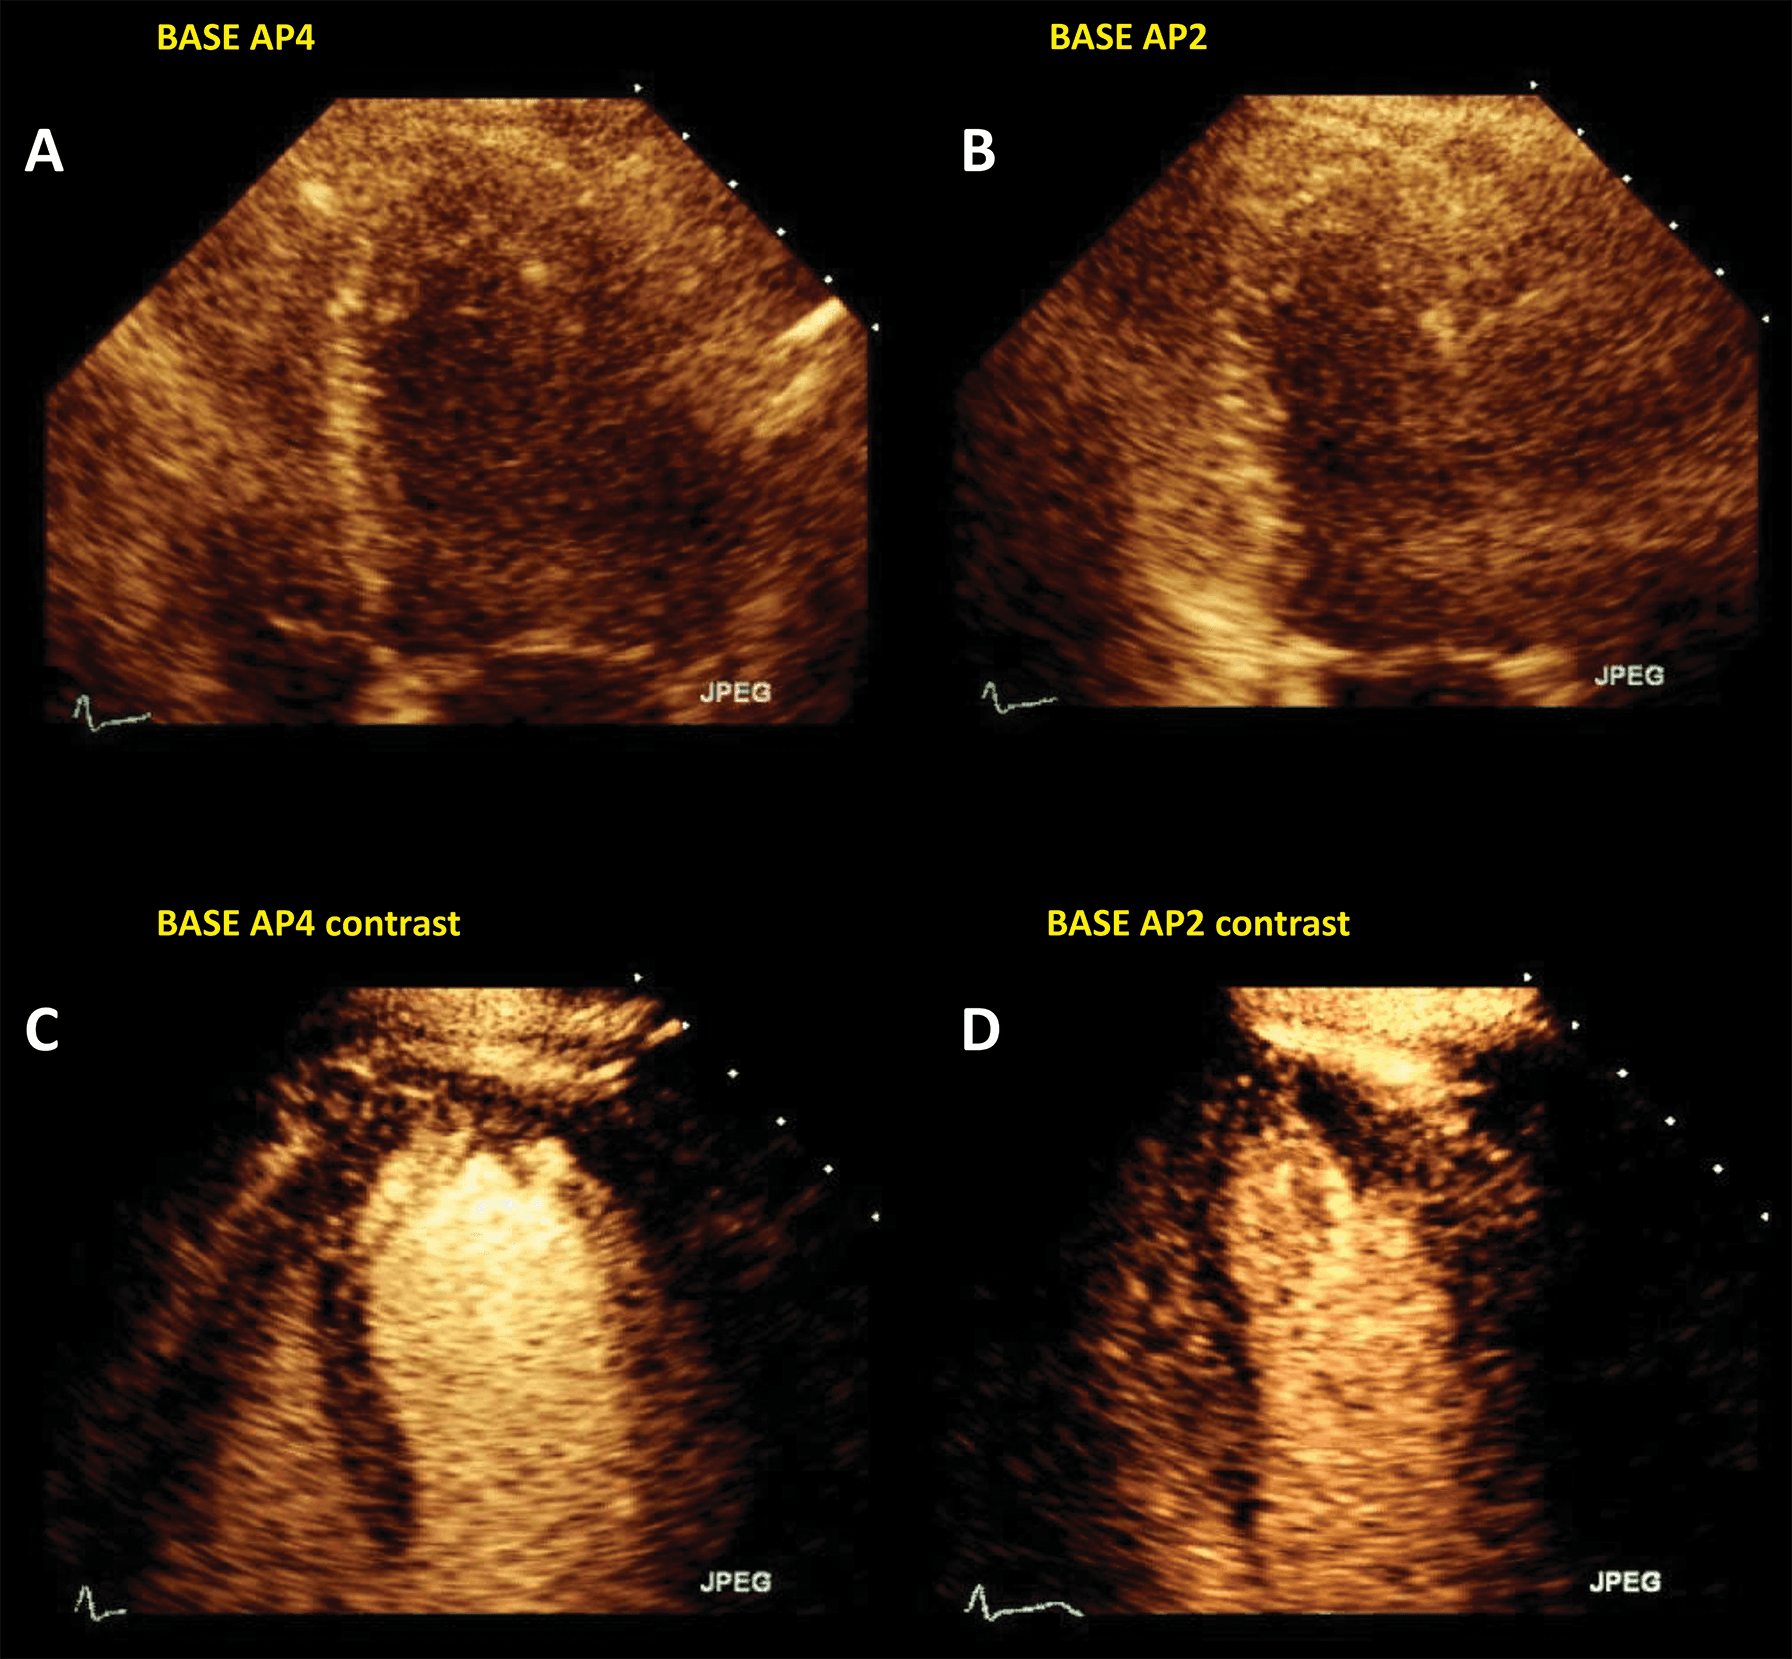

The largest body of evidence for MEE concerns the indication for LVO for enhancing the endocardial borders [10, 11, 12, 13, 14, 15]. This is achieved by using repetitive intravenous boluses of UEA, and sometimes continuous low-dose infusion. Guidelines indicate the use of LVO to enhance the endocardial borders in cases when the LV dimensions, function or regional wall motion cannot be accurately assessed using non-enhanced ultrasound [7, 14]. The general “rule of thumb” is to use microbubble UEA in cases where two or more contiguous myocardial segments are not properly visualized with non-enhanced ultrasound [13]. Of course, recent years have seen tremendous improvement in image quality for clinical ultrasound systems. But despite the introduction of harmonic imaging as a standard, some images remain non-diagnostic (Fig. 2). Moreover, harmonic imaging represented a significant leap in MEE [16, 17], leading to the present-day contrast-specific imaging modalities.

Fig. 2.Left ventricular opacification (LVO) for endocardial border delineation. Example of baseline non-enhanced echocardiography images in apical 4-chambers (A) and apical 2-chambers (B) views, where the visualization of the endocardium is suboptimal over several segments. After intravenous injection of a bolus of UEA, there is full opacification of the LV cavity, with clear delineation of the endocardium in all segments (C, D). Source: personal collection.